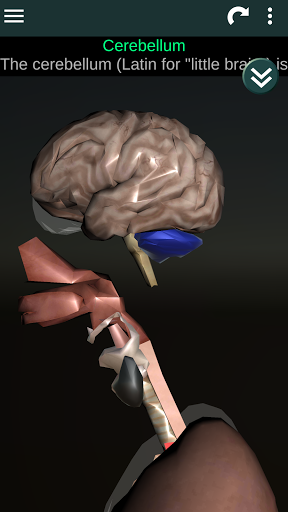

Internal Organs in 3D Anatomy لـ Vodafone Smart N9 Lite

(الأجهزة الداخلية في)

Internal Organs 3D Anatomy 3.4

يمكنك هنا تنزيل ملف حزمة تطبيق أندرويد "Internal Organs 3D Anatomy" الخاصة بجهازVodafone Smart N9 Lite مجانًا، نسخة ملف حزمة تطبيق أندرويد - 3.4 للتحميل على Vodafone Smart N9 Lite اضغط ببساطة على هذا الزر. إنه سهل وآمن. نحن نقدم فقط ملفات حزمة تطبيق أندرويد الأصلية. إذا انتهكت أية مواد موجودة في الموقع حقوقك قم بإبلاغنا من خلال